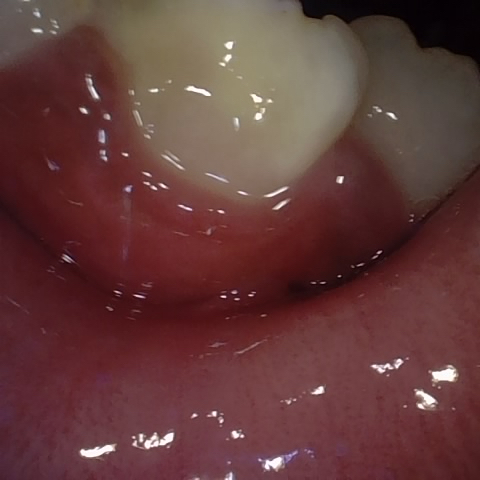

Image 1078 / 1103

NHD39174

Annotated as "Good"

Original Image Rendering Image